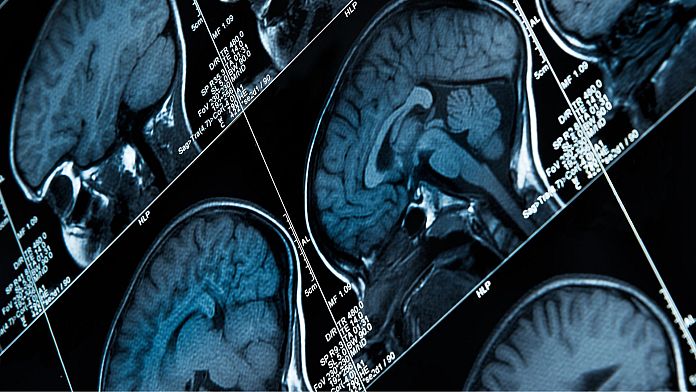

I ricercatori hanno identificato un’area del cervello associata al dolore cronico, facendo sperare in nuovi trattamenti.

I ricercatori hanno registrato per la prima volta segnali cerebrali per il dolore, utilizzando una tecnica di apprendimento automatico che potrebbe portare a trattamenti per la condizione.

Questo studio ha esaminato direttamente i cambiamenti nell’attività cerebrale in due regioni del cervello – la corteccia cingolata anteriore (ACC) e la corteccia orbitofrontale (OFC) – dove si pensa che si verifichino risposte al dolore, mentre i pazienti hanno riferito autonomamente i loro livelli di dolore.

Sono stati impiantati chirurgicamente con elettrodi mirati ai loro ACC e OFC. Un certo numero di volte al giorno i partecipanti hanno risposto a domande sul loro dolore e hanno avviato una registrazione cerebrale che ha fornito un’istantanea dell’attività nelle due aree cerebrali. L’analisi dell’apprendimento automatico è stata quindi utilizzata per prevedere lo stato di dolore cronico dei partecipanti.